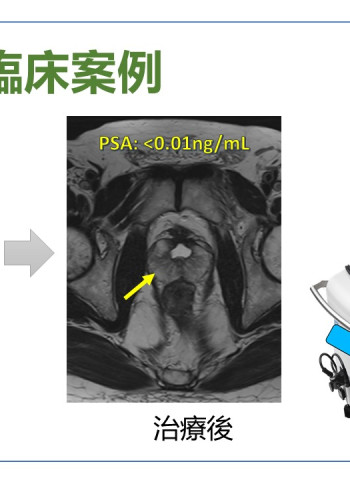

奇美醫院海福刀無創手術 結合即時影像 精準摧毀癌細胞

記者蘇旋/報導 彪網媒 中華超傳媒